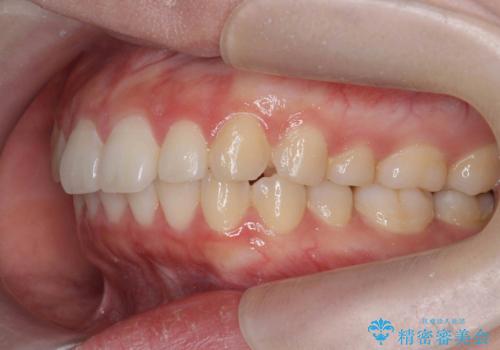

矯正治療を途中でやめてしまった、途中からの治療希望

- 他院での矯正治療中に行かなくなってしまい、装置をつけたまま矯正治療の続きを希望され来院されました。

マウスピースでは並べることが難しい左下の奥歯を部分ワイヤー矯正で並べたのち、マウスピース矯正装置インビザラインで歯並びを整えていきます。